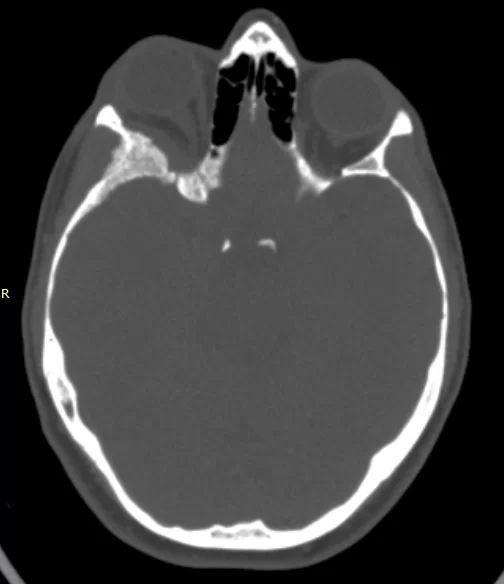

Η μετεγχειρητική αξονική τομογραφία εγκεφάλου ανέδειξε τη γενναιόδωρη αποσυμπίεση του κόγχου.

Μετεγχειρητικά η ασθενής παρουσίαζε άριστη νευρολογική εικόνα, χωρίς καμία επιδείνωση της όρασης.